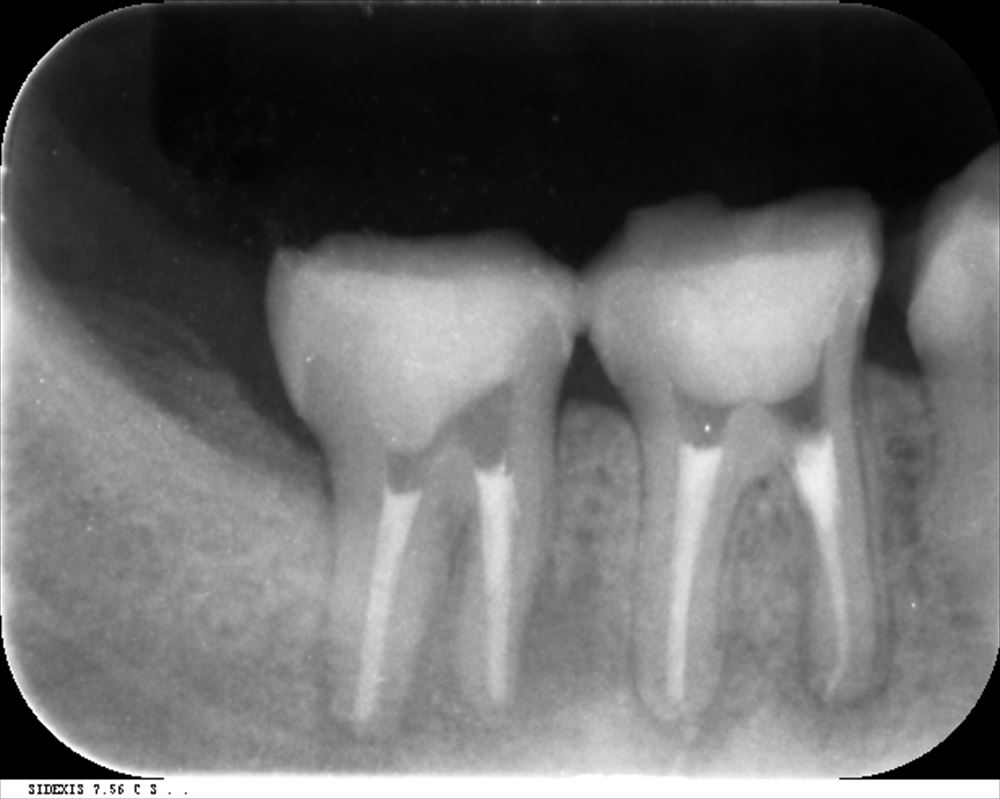

厳密に根管充填

症状も腫れもなく本人笑顔!!!比較写真

この様に当院では保存治療を専門に治療を行っております。